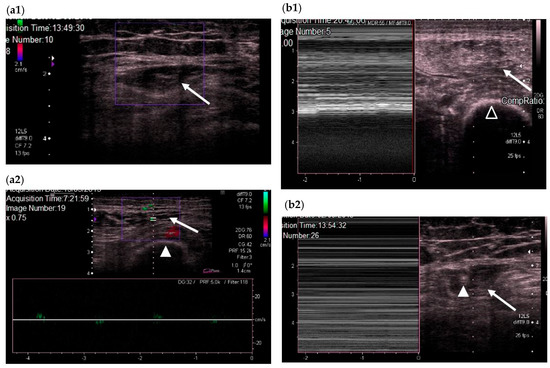

We subsequently used color Doppler to evaluate QRF vascularization and M-mode to establish the presence or absence of fasciculations (Figure 3) [18].

Figure 3.

(a) Transversal QRF muscle US scan and color Doppler. (a1) QRF muscle without vascularization (echogenicity Category 3). (a2) QRF muscle with vascularization (echogenicity Category 2): the femur (arrowhead) and the QRF muscle (arrow). (b) Transversal US scans and M-mode; (b1) QRF muscle (arrow) with fasciculations (echogenicity Category 2) and the femur (black arrowhead); (b2) QRF muscle without fasciculations (echogenicity Category 3). QRF tendon of 3.6 mm (white arrowhead) and the QRF muscle (arrow). QRF: quadriceps rectus femoris, US: ultrasound.